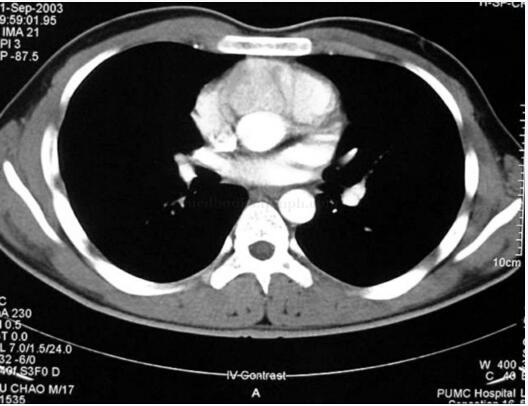

肾上腺CT未见异常;UCG未见心脏肿瘤;MIBG未见嗜铬细胞瘤征象;奥曲肽显像提示心脏内放射性浓聚区;再次复查UCG提示主动脉起始部前壁直径cm左右肿物,突出于右室流出道;CT示主动脉前壁肿瘤,与周围结构分界不清图31-1);MR(T2像)示主动脉前壁肿瘤,与周围结构分界不清(图31-2);冠状动脉造影(RCA)示右冠状动脉近段被肿物压迫闭塞,可见肿物血管影。

图31-1 CT示主动脉前壁肿瘤